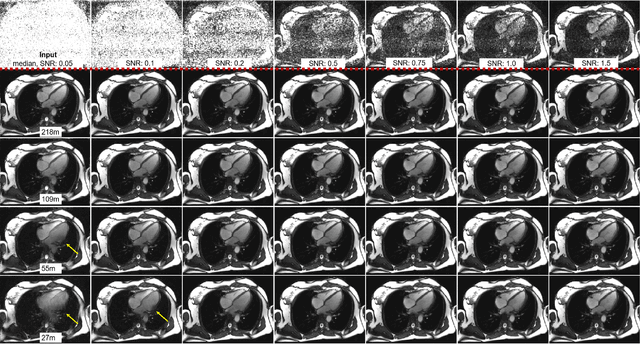

Abstract:Purpose: To propose a flexible and scalable imaging transformer (IT) architecture with three attention modules for multi-dimensional imaging data and apply it to MRI denoising with very low input SNR. Methods: Three independent attention modules were developed: spatial local, spatial global, and frame attentions. They capture long-range signal correlation and bring back the locality of information in images. An attention-cell-block design processes 5D tensors ([B, C, F, H, W]) for 2D, 2D+T, and 3D image data. A High Resolution (HRNet) backbone was built to hold IT blocks. Training dataset consists of 206,677 cine series and test datasets had 7,267 series. Ten input SNR levels from 0.05 to 8.0 were tested. IT models were compared to seven convolutional and transformer baselines. To test scalability, four IT models 27m to 218m parameters were trained. Two senior cardiologists reviewed IT model outputs from which the EF was measured and compared against the ground-truth. Results: IT models significantly outperformed other models over the tested SNR levels. The performance gap was most prominent at low SNR levels. The IT-218m model had the highest SSIM and PSNR, restoring good image quality and anatomical details even at SNR 0.2. Two experts agreed at this SNR or above, the IT model output gave the same clinical interpretation as the ground-truth. The model produced images that had accurate EF measurements compared to ground-truth values. Conclusions: Imaging transformer model offers strong performance, scalability, and versatility for MR denoising. It recovers image quality suitable for confident clinical reading and accurate EF measurement, even at very low input SNR of 0.2.